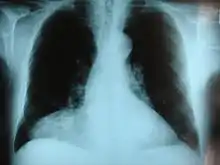

![]() | |

| Morgagni hernia seen on a chest radiograph. | |